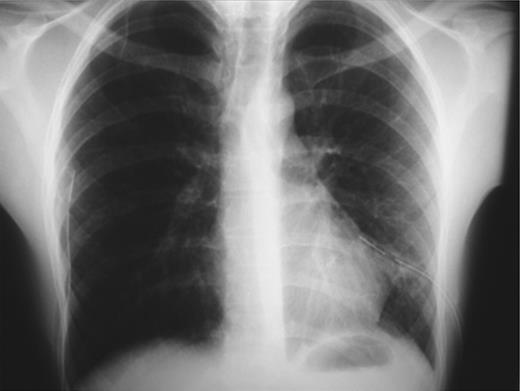

On emergency basis, the patient was managed with bilateral tube thoracostomy through the fifth intercostal spaces. During hospitalization, both lungs were gradually expanded; the use of continuous aspiration was necessary for a couple of days, in order to achieve complete expansion of the left lung (Fig. 2). Both chest tubes were removed on the fifth day of hospitalization. Next day the plain X-ray revealed recurrence of pneumothorax on the left side (Fig. 3). A chest tube was reinserted. Continuous suction was used and complete expansion of the left lung was succeeded. The tube was removed after 5 days; no recurrence took place at this time. During the next 3 days the patient remained under observation; serial physical examinations and chest X-rays were normal and the patient was discharged home.

Complete bilateral lung expansion after insertion of chest tubes.